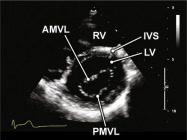

| 2.11. Mặt cắt trục ngắn cạnh ức (ngang mức van hai lá) |

||||||||

|

|

Cửa sổ siêu âm cạnh ức

Mặt cắt trục ngắn cạnh ức Từ vị trí các đại động mạch gập đầu dò xuống dưới |

Thất phải (RV) Vách liên thất (IVS)

Lá trước van hai lá (AMVL) Lá sau van hai lá (PMVL) Thất trái (LV) |

|||||